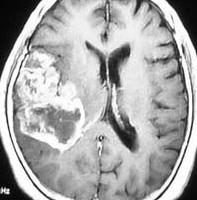

40歳くらいの成人に発生したもので,この大きさですが局所症状はなく頭痛のみです。組織診断では,コアは膠芽腫ですが,周囲はグレード2のびまん性星細胞腫の診断でした。全摘出と放射線治療で4年間無症状でした。これは古い例なのですが,現在では膠芽腫に分類されないものなのでしょう。